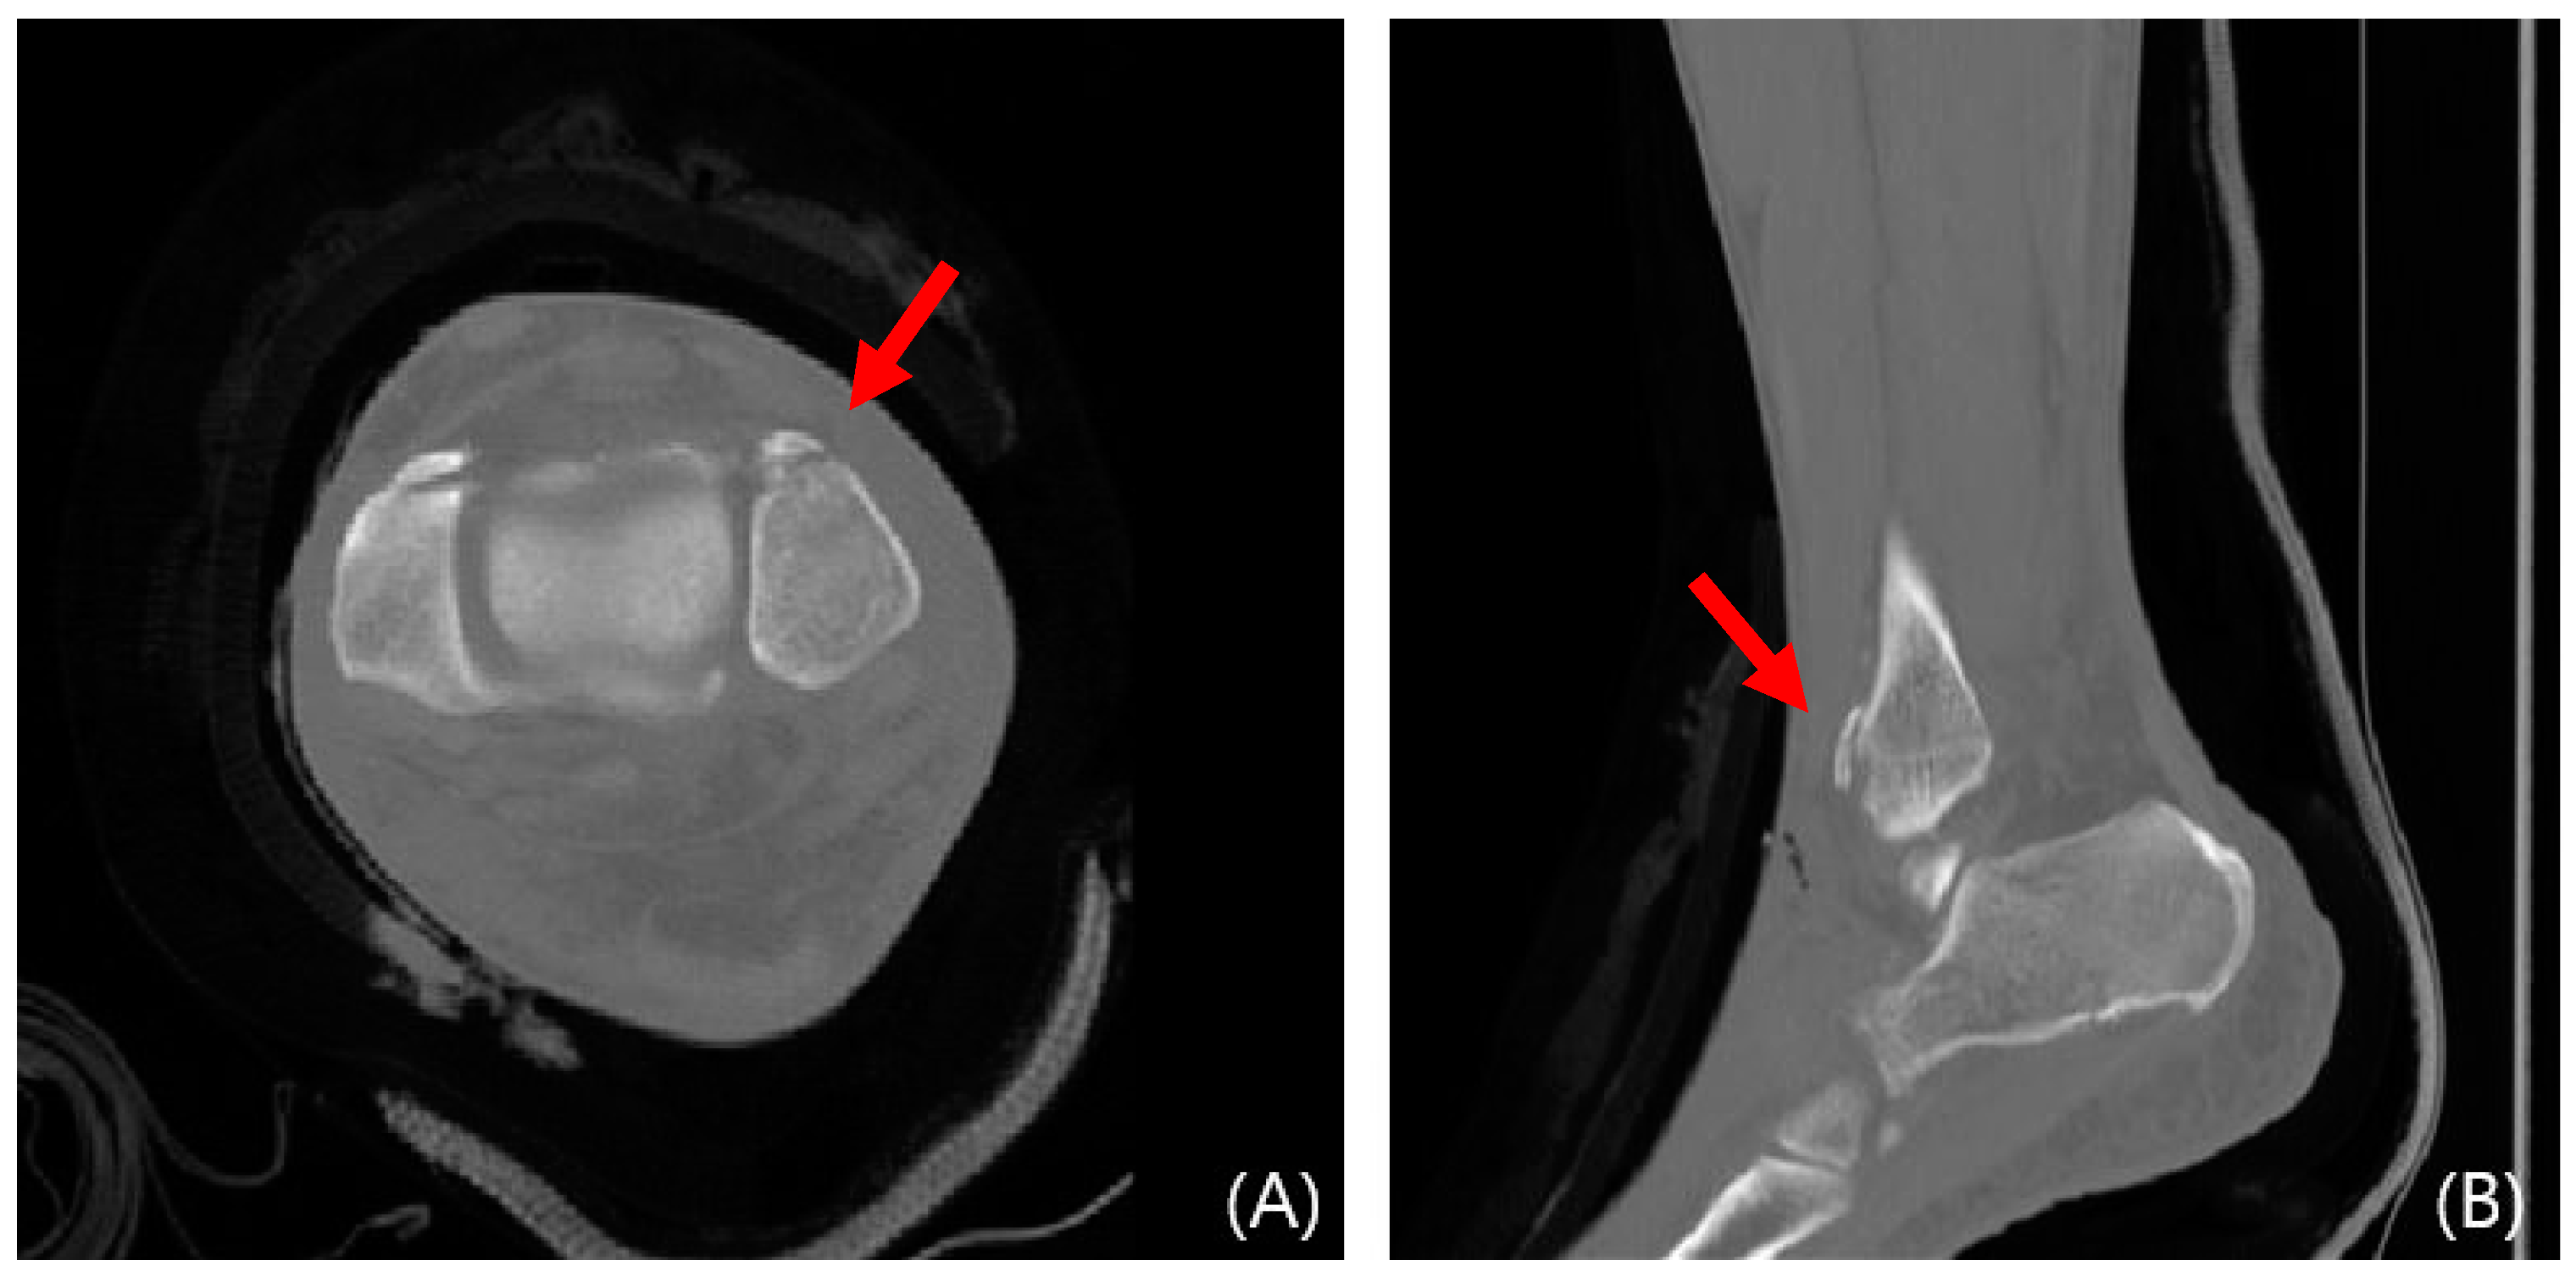

This study evaluated syndesmosis reduction by analyzing postoperative axial CT images captured 1 cm proximal to the tibial plafond (Table 1 and Figure 1) [16,17,18,19]. Four radiographic measurements were chosen and assessed with a PACS image viewer software (Dejaview2 version 1.0, Dongwun Information Technology, Republic of Korea). Two independent observers, blinded to patients’ clinical outcomes and current complaints, objectively evaluated the measurements. The process was repeated after a 6-week interval to ensure reliability.

In cases of instability, a mini-plate (Arix Hand System, Jeil Medical, Seoul, Republic of Korea) is shaped to cover the Wagstaffe fracture and secured using 2.0 mm cortical screws and locking screws (Figure 3). For smaller fractures, screws were applied to the proximal and distal sections of the mini-plate at the fracture site. Screw fixation was performed at the fracture site when possible (Figure 4). Subsequently, tibiofibular joint stability was assessed through arthroscopy. Figure 5 and Figure 6 show the preoperative plain X-ray and CT images of a 47-year-old female with a Wagstaffe fracture. Figure 7 shows the postoperative plain X-ray image of a Wagstaffe fracture treated with open reduction and internal fixation using the described technique. Postoperative CT images were used to further confirm the reduction and fixation (Figure 8).

Figure 1. Radiologic measurements. (Red line) (a) Direct anterior difference and direct posterior difference. (b) Fibular translation. (c) Fibular rotation (Red line).

Figure 6. Preoperative CT images of a 47-year-old female with a Wagstaffe fracture (red arrow). Axial (A) and sagittal (B) views.